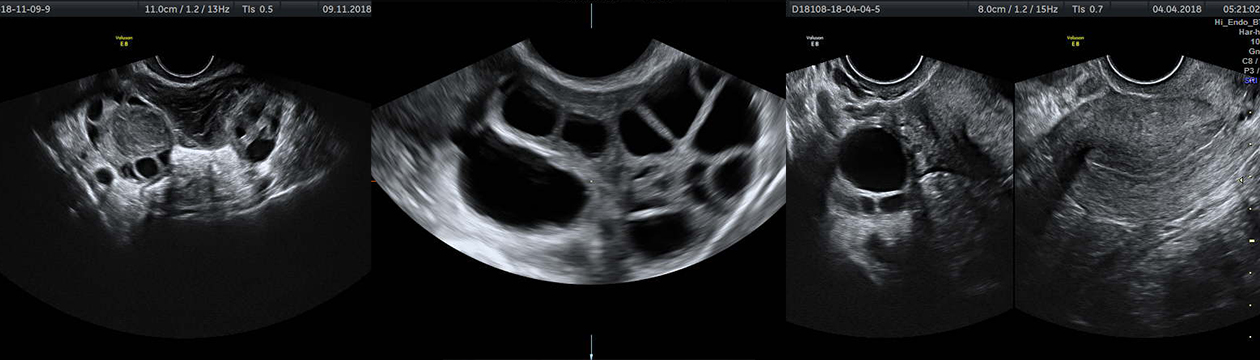

Crnobijeli ili 2D (dvodimenzionalni) ultrazvučni pregled

Ovo su standarni pregledi kojima dobijamo informacije o veličini, strukturi, obliku materice, jajnika, te o eventualnim drugim promjenama u maloj karlici žene čime vrlo brzo postavljamo dijagnozu kad je u pitanju najveći broj ginekološki oboljenja i poremećaja kao što je izostanak menstruacije, krvarenja i razni drugi menstrualni pormećaji.